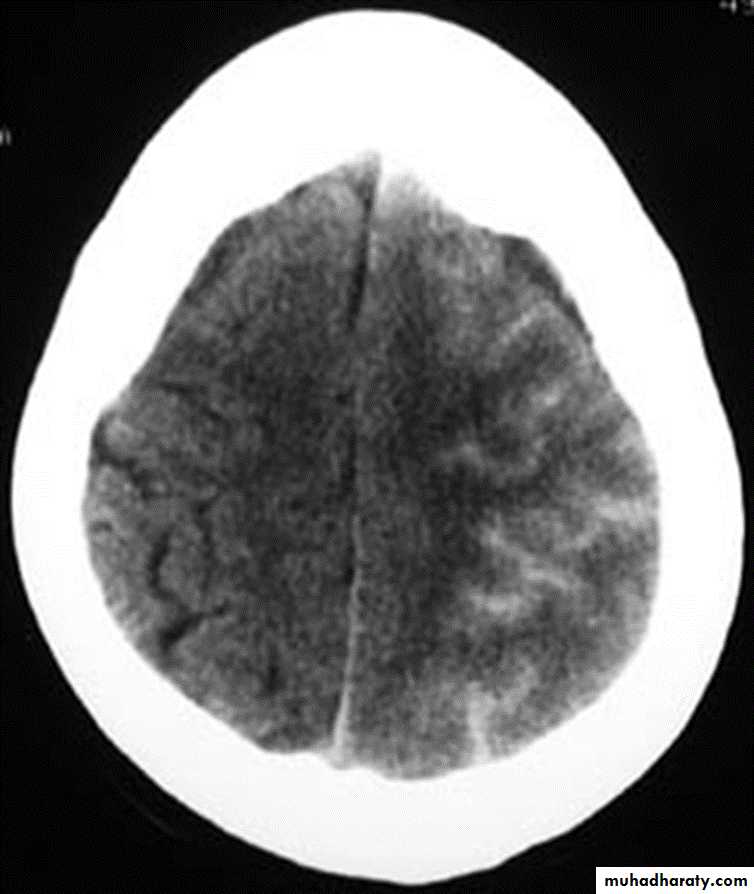

Caused by accelerate high speed impact resulting into tearing of bridging veins or bleeding from cortical vessels, venous sinuses. acute brain trauma may coexist with altered level of consciousness and focal neurological deficit are common. Diagnosis is by CT(crescent hyperdense extraaxial mass) and rapid evaluation are necessary. the treatment depends on many factors such If no signs of rapid deterioration or progressive neurological deficit with no mass effect on CT so observation and control of intracranial p. is necessary, otherwise surgery is the role)

Mostly occurs in those over 50 years old,½ of patients have got no history of trauma (If there is any history of trauma then it is trivial), Alcoholism, epilepsy, coagulopathy are common, Dementia is common presentation. The treatment is medical In minimal neuological deficit. If not successful or with deterioration of neurological picture so surgery is the role by burr hole evacuation.( the CT picture is hpodense crescent exraaxial mass)Extradural hematomas

Mostly resulting from meningial vessel tear (arteries > Veins > sinuses) and Fractures are common associated injury. Severe associated brain injury is rare. Usually the Level of consciousness is variable(lucidity interval is common). The haematoma with mass effect must be evacuated within ½ hour. if small follow up is recommended. The Prognosis depends on level of consciousness at time of presentation ( C picure is that of biconvex or lense hyperdense exrtracranial mass)

It is a macroscopical focal laceration of brain tissue. Level of consciousness depends on size of contusion and location and the CT picure is that of irregular focal mixed densi intraaxial mass. Therec are 3 types, coupe, counter coupe and intermediate coupe). Small and deep ones needs follow upwhile Large with mass effect ones need lobectomy. the Large one may herniate as late as 9 days post trauma.Subarachnoid bleeding

CT scan : almost without exception , an unenhanced (i.e.- non – contrast ) CT scan of brain suffices for patients seen in emergency department presenting after trauma or with new neurological deficit .The main emergent conditions to rule out :

1. blood ( hemorrhages or hematomas(

a. EDH ( extradural hematoma (

b. SDH ( subdural hematoma (

c. subarachnoid hemorrhage

d. intracerebral hemorrhage

3.evidence of cerebral anoxia , loss of gray –white interface

7. shift of midline structures